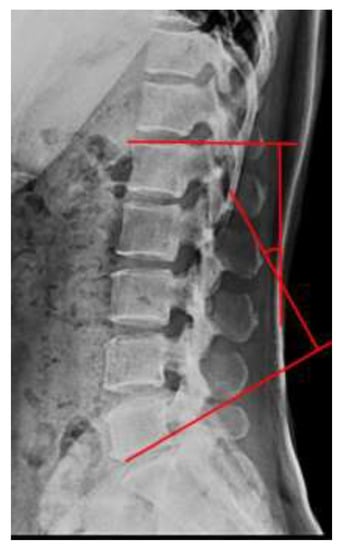

2.3. Cobb’s Angle

| LLA (°) | Pre | 33.17 ± 1.85 | 33.50 ± 1.62 | 32.75 ± 2.09 | 32.960 *** | a > c *** a > b ** b > c *** |

| Post | 40.25 ± 2.73 ††† | 37.17 ± 1.95 ††† | 32.5 ± 2.32 | |||